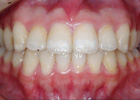

歯を抜かずに治療ができた例

治療前

治療後